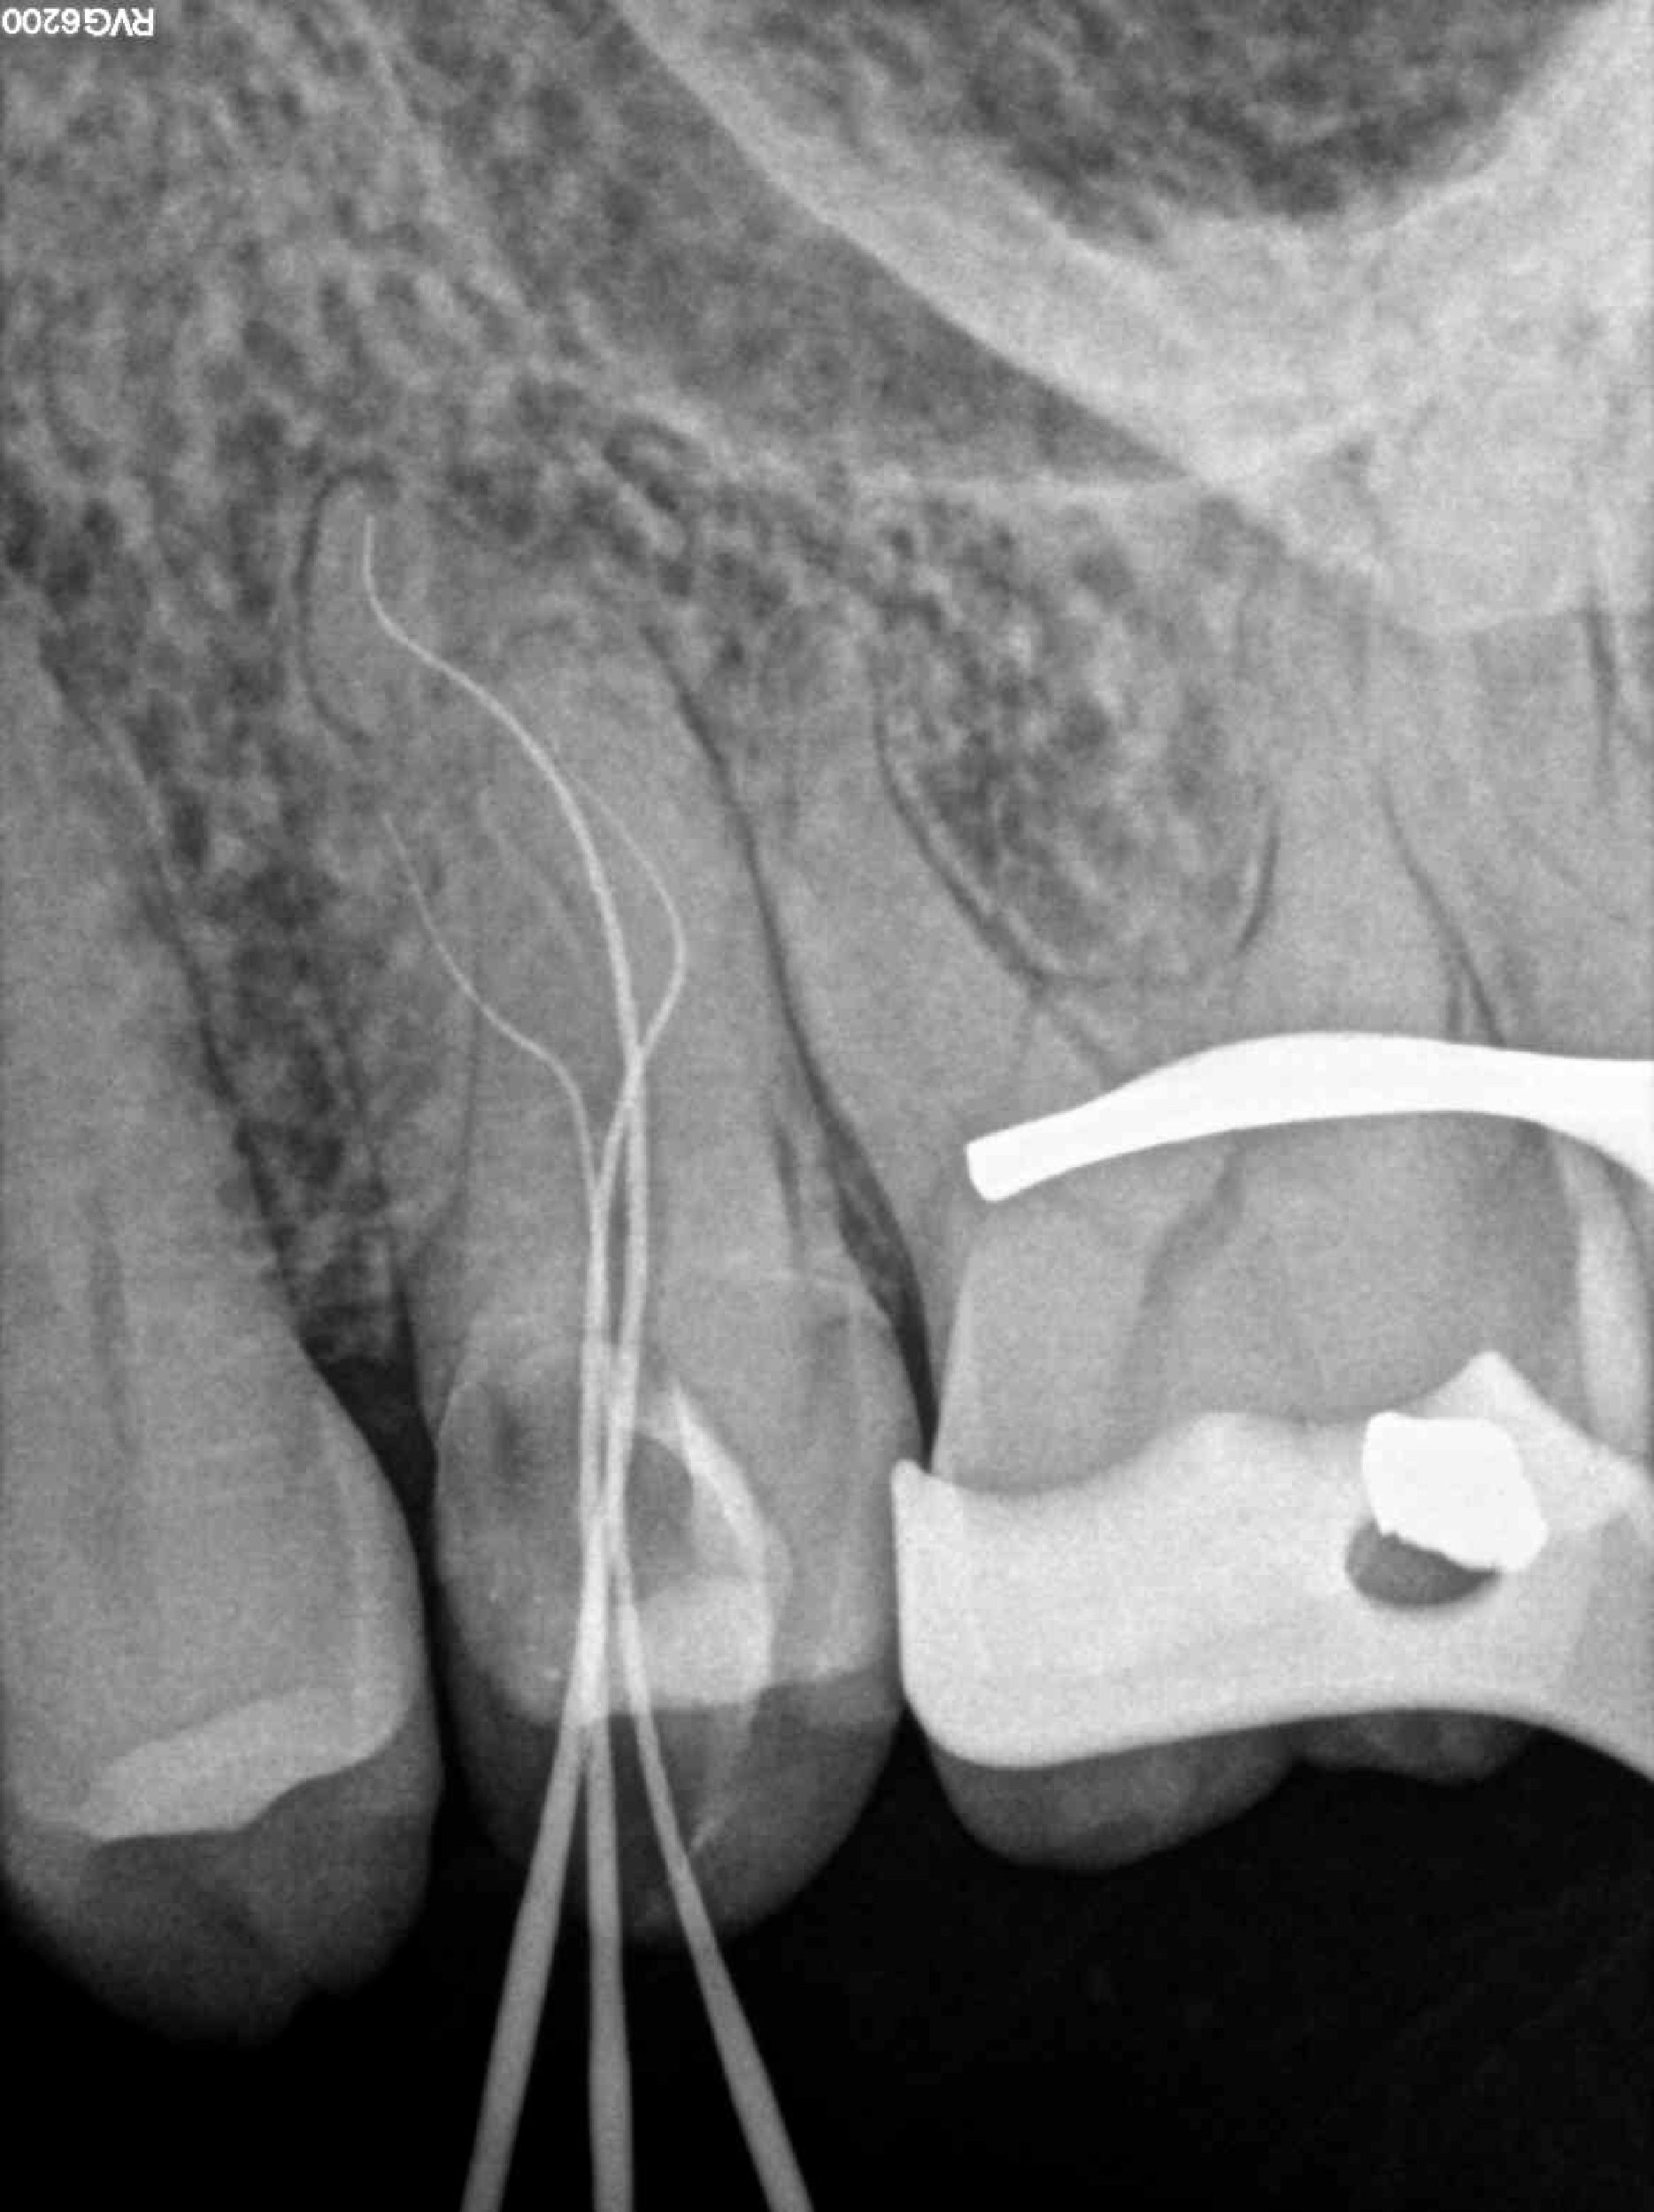

* Haz click sobre las radiografías para verlas a mayor tamaño

Haz click sobre las radiografías para verlas a mayor tamaño